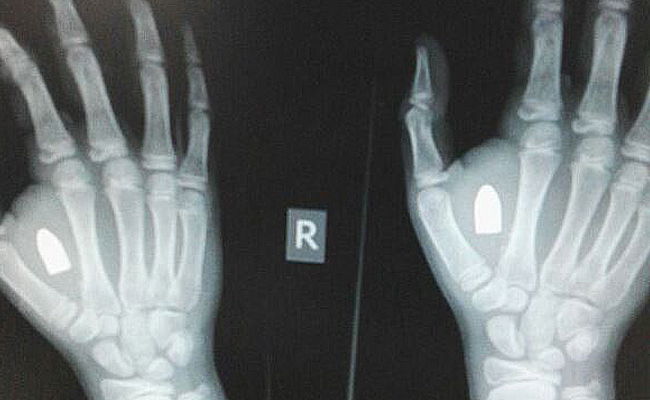

כעת, כאשר כף היד החל להתנפח ולכאוב, הגיע הילד לבדיקה שם ערך לו הצוות צילום רנטגן שאבחן - להפתעת כולם - כי מדובר בקליע שנתון בתןף כך ידו של הילד.

ילד בן 11 התלונן על כאב ונפיחות בכף ידו לאחר בדיקה התברר כי מדובר בקליע שחדר לכף ידו.